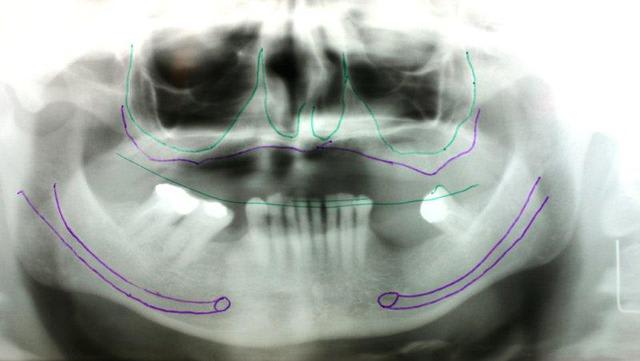

Au maxillaire il faut faire une implanto totale et stt ne pas garder les canines

A la mandibule faut disker mais ça va

PS il faut d abord faire réaliser des modèles stéréolithographiques par Materialise pour se prononcer au final

Pcq ds ces cas là onne sait pas faire autrement

1. les palques ont une assisse énorme par rapport à 7 cylindres

2. la résorption centripède du maxillaire le rend trop petit pour en poser plus

De plus malgré le grand overjet , on a qd même un implant central qui soutient l arc incisif, même s il est 2 cm en arrière de la ligne des dents

> 2. la résorption centripède du maxillaire le rend trop petit pour en poser plus